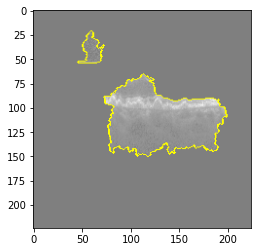

Original Image

Explanation B

Explanation C

Explanation D

GradCAM

Fig 6, 7, 8 and 9 depicts the visualization of correct predictions by our proposed CNN model where fig 6 is class CNV, fig 8 is class DME, fig 7 is DRUSEN and finally, fig 9 is NORMAL. Here the first photo in every class is the original image. The LIME map of our suggested model’s prediction is shown in image B whereas in image C the positive region is highlighted in specific sections on the original image. For Image D we have increased the number of features from 5 to 10 thus more regions have been predicted as the positive region which is highlighted in green. After increasing the features from 5 to 10, some of the regions are predicted wrongly. The red regions represent the output of incorrect prediction. The following image represents the Grad-CAM heatmap highlighting the regions with our model’s prediction.